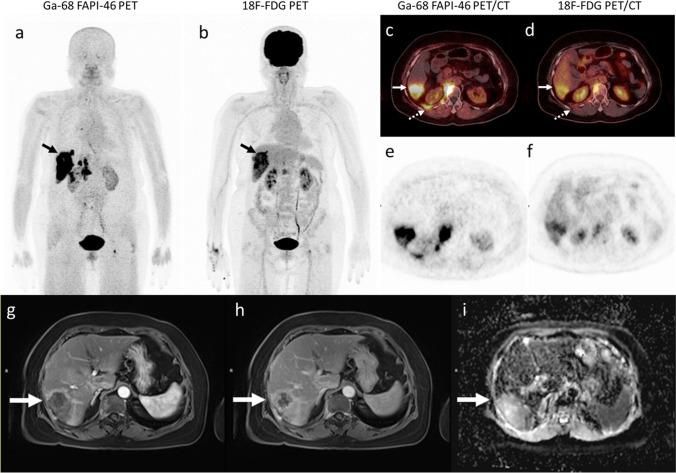

The 27 patients had a median age of 68 years (interquartile range: 60-74 years; 21 men). Primary intrahepatic tumours were reported in 13 patients (15 imaging studies) with cholangiocarcinoma (CCA) and in 14 patients with hepatocellular carcinoma (HCC). All intrahepatic lesions detectable on MRI were also detected on [ Ga]Ga-FAPI-46 PET/CT giving a sensitivity of 100% (19/19), whereas the sensitivity of [F]FDG PET/CT was 58% (11/19). All intrahepatic lesions were detected on [ Ga]Ga-FAPI-46 PET/CT, on which they showed higher activity (median SUVmax: 15.61 vs. 5.17; P < .001) and higher target-to-background ratio (TBR; median, 15.90 vs. 1.69, P < .001) than on [F]FDG, especially in patients with CCA (median TBR, 21.08 vs. 1.47, respectively; P < .001). The uptake positivity rate in regional node metastasis was 100% (12/12) on [ Ga]Ga-FAPI-46 PET/CT compared with 58% (7/12) on [F]FDG PET/CT. All patients with distant metastasis (100%, 14/14) were detected on both [F]FDG and [ Ga]Ga-FAPI-46 PET/CT imaging, although more distant metastatic lesions were detected on [ Ga]Ga-FAPI-46 PET/CT than on [F]FDG (96% (42/44) vs. 89% (39/44), respectively).

27 例患者的中位年龄为 68 岁(四分位距:60-74 岁;21 例男性)。13 例患者(15 项影像学研究)报告原发性肝内肿瘤为胆管细胞癌(CCA),14 例患者为肝细胞癌(HCC)。MRI 上可检测到的所有肝内病变在 [68Ga]Ga-FAPI-46 PET/CT 上也均有检出,其灵敏度为 100%(19/19),而 [F]FDG PET/CT 的灵敏度为 58%(19/19)。所有肝内病变在 [68Ga]Ga-FAPI-46 PET/CT 上均有检出,在该检查中它们显示出更高的活性(中位 SUVmax:15.61 比 5.17;P<0.001)和更高的靶-背景比(TBR;中位数,15.90 比 1.69,P<0.001),尤其是在 CCA 患者中(中位 TBR,分别为 21.08 比 1.47;P<0.001)。在区域淋巴结转移中,[68Ga]Ga-FAPI-46 PET/CT 的摄取阳性率为 100%(12/12),而 [F]FDG PET/CT 的摄取阳性率为 58%(7/12)。所有远处转移患者(100%,14/14)在 [F]FDG 和 [68Ga]Ga-FAPI-46 PET/CT 成像上均有检出,尽管 [68Ga]Ga-FAPI-46 PET/CT 比 [F]FDG 检测到更多的远处转移病灶(96%(42/44)比 89%(39/44))。